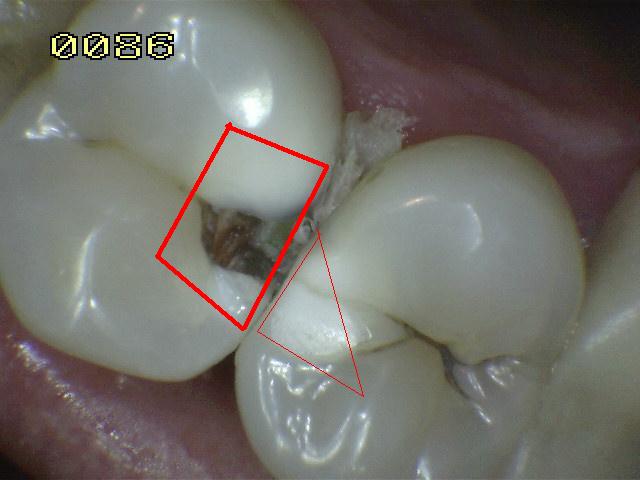

¿Determine los códigos pertinentes a cada imagen?

Click en el hipervínculo: Para comparar el resultado de su diagnóstico